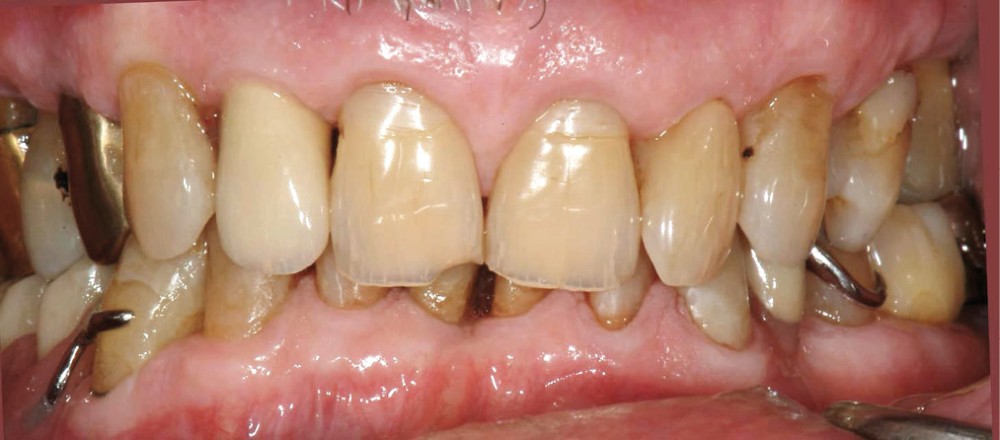

La prothèse partielle à armature métallique mandibulaire (PPAM) et la restauration du secteur antérieur à l’aide de matériau composite ont été réalisées en 2007. Le patient présente une occlusion de type classe II d’Angle génératrice de sévères abrasions du secteur incisif mandibulaire. Sur les photographies initiales (fig. 1a, b), on constate les prémices de traumas occlusaux (fracture de l’angle de 11, érosions des collets restaurés précédemment).